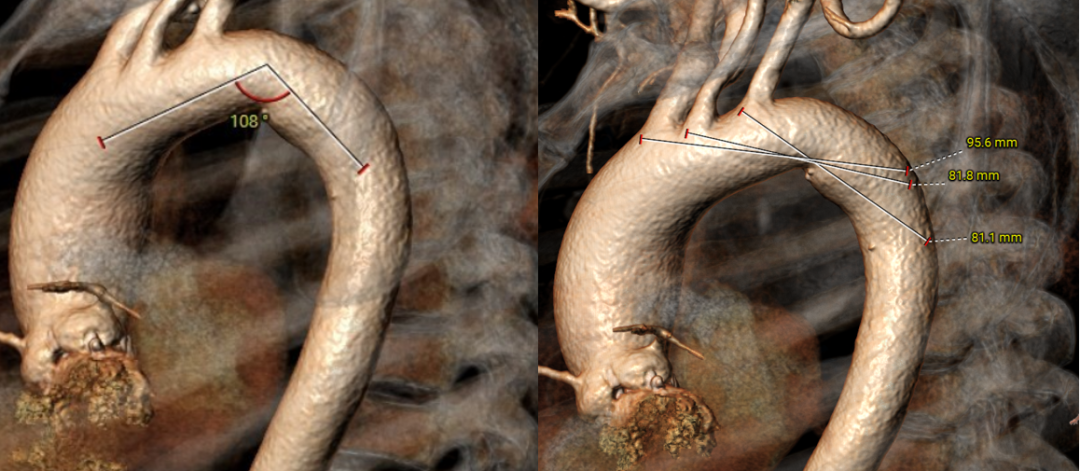

主动脉弓角度可,大弯侧无明显钙化,升主扩张。

外周血管入路评估:左侧入路最窄处内径7.6 mm,右侧入路最窄处内径7.7 mm;右侧入路股动脉分叉高度可,迂曲程度可。

血管入路评估:主动脉弓钙化,左侧股动脉入路最窄处内径8.6mm,右侧股动脉入路最窄处内径8.0mm;左右股动脉分叉高度可,入路未见迂曲。

升主MAX处均径44.9 mm,瓣环角度67°。

升主MAX处均径46.1 mm;瓣环角度41°。